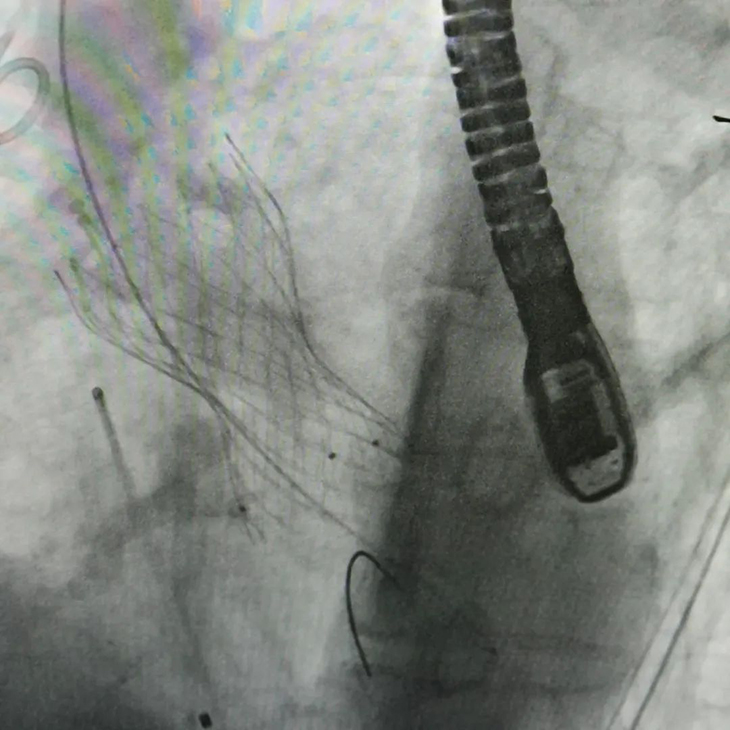

何学志、庄熙晶带领心外科团队进行TAVI手术

介入导管室技师长石峻在术中通过应用三维医学影像融合技术精准定位靶位,有效缩短手术时间。

经过团队的共同努力和默契配合,两位患者术中生命体征平稳,主动脉瓣膜支架形态良好,功能正常,手术顺利完成。每台手术平均用时两小时,不仅时间上比传统开胸手术减少了2-3个小时,也避免了体外循环对于机体的影响,减少了术后并发症的发生。